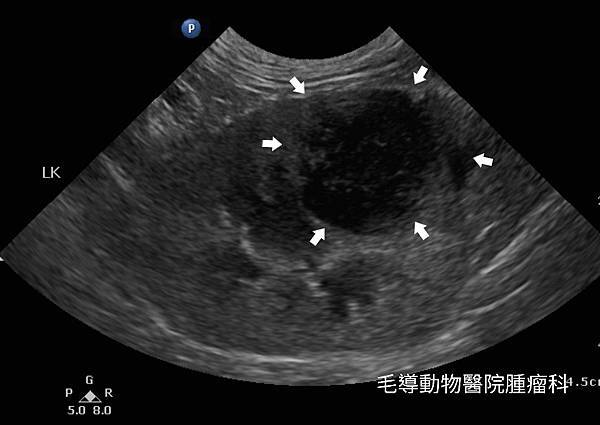

貓腎臟淋巴瘤

淋巴瘤為貓腎臟腫瘤中最常見的一種惡性腫瘤,貓愛滋(FIV)及貓白血病(FeLV)與罹病風險相關。貓腎臟淋巴瘤常見雙側腎臟都被侵犯,而一般理學檢查及血檢與其他的腎臟疾病類似,需藉由影像學檢查(超音波)和細胞學檢查來區別診斷。